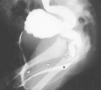

Objetivo: Ilustrar el espectro de hallazgos radiológicos de las duplicaciones del tracto urinario y mostrar la eficacia de los ultrasonidos, la cistouretrografía miccional seriada (CUMS), la urografía intravenosa (UIV), el estudio isotópico y la resonancia magnética (RM) en el manejo de estas entidades. Material y métodos: Hemos revisado retrospectivamente los hallazgos radiológicos de las duplicaciones del riñón, uréter, vejiga y uretra a partir de los datos de nuestro archivo de patología genitourinaria pediátrica. Todos los casos cuentan con estudio ecográfico, mientras que la CUMS, la UIV, el estudio isotópico y la RM se realizaron en función del tipo de duplicación. Hacemos hincapié en las bases embriológicas de los hallazgos radiológicos que, cuando fue posible, se cotejaron con los hallazgos anatomopatológicos. Resultados: Las duplicaciones completas o incompletas afectaron con más frecuencia al sistema pielocalicial y al uréter (pelvis renal bífida, uréter semibífido, uréter bífido bajo, duplicación ureteral completa y triplicación). Las duplicaciones vesicales se muestran en los planos sagital y coronal, aunque la forma más frecuente fue la división sagital con dos vejigas resultantes contiguas separadas por un pliegue peritoneal con tejido areolar fino. Las duplicaciones uretrales o las uretras accesorias se dieron fundamentalmente en el plano coronal; sin embargo, también describimos la duplicación en el plano sagital en ausencia de duplicación vesical. Mostramos un caso extremadamente raro de duplicación completa de uretra femenina. Conclusión: Mostramos una visión de conjunto de las duplicaciones del tracto urinario y discutimos la utilidad de varias técnicas de imagen disponibles. Dado que estas entidades tienen una apariencia radiológica característica, este artículo puede ser útil para comprender mejor estas anomalías.

Objective: To illustrate the spectrum of imaging findings for urinary tract duplications and to show the efficacy of ultrasonography (US), voiding cystourethrography (VCU), intravenous urography (IVU), scintigraphy, and magnetic resonance (MR) in the management of these entities. Material and methods: We have reviewed the imaging findings for cases of renal, ureteral, vesical, and/or urethral duplication from our pediatric genitourinary pathology archive. All patients underwent US examination; VCU, IVU, scintigraphy, and MR studies were performed in function of the type of duplication. We explain our findings within the framework of embryological development and correlate the imaging findings with the histopathologic findings whenever possible. Results: Complete or partial duplications most commonly affected the pyelocalyceal system or the ureters (bifid renal pelvis, bifid mid-ureter, low bifid ureter, complete ureteral duplication and triplication). Vesical duplications are shown in the sagittal and coronal planes, although the most common presentation was sagittal division resulting in two contiguous bladders separated by a peritoneal fold with thin areolar tissue. Ureteral duplication or accessory ureters were mostly seen in the coronal plane; however, we also describe duplication in the sagittal plane in the absence of vesical duplication. We show an extremely rare case of complete duplication of the female urethra. Conclusion: We provide an overview of the set of urinary tract duplications and discuss the usefulness of the different imaging techniques available for each type. As these entities have a typical radiological appearance, this article can help to understand these anomalies better.